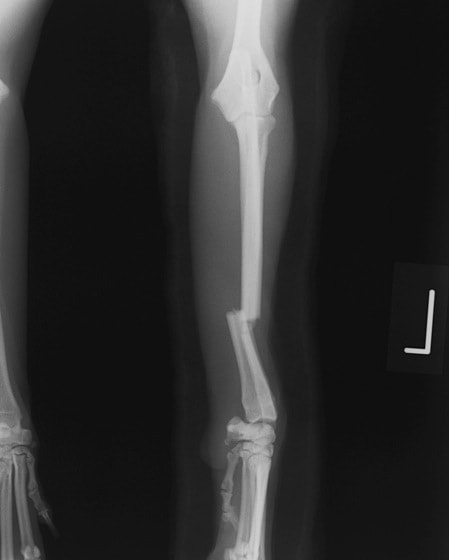

橈尺骨骨折 : 症例1 | 症例2 | 症例3 | 症例4 | 症例5 | 症例6 | 症例7

: 症例8 | 症例9 | 症例10 | 症例11 | 症例12 | 症例13 | 症例14

: 症例15 | 症例16 | 症例17 | 症例18 | 症例19 | 症例20 | 症例21